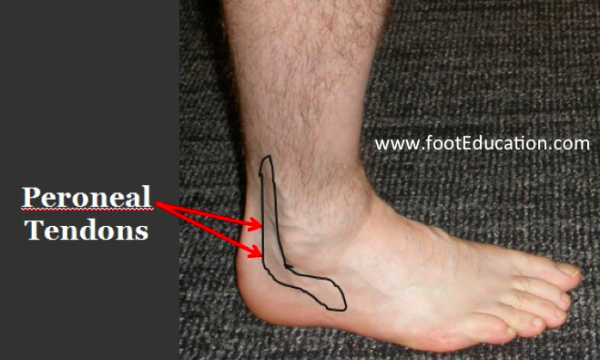

Peroneal tendonitis store, Peroneal Tendonitis FootEducation store

Peroneal Tendonitis FootEducation